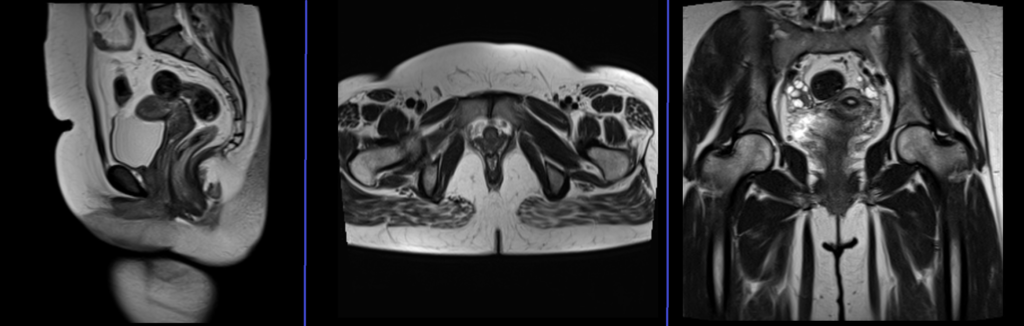

localiser

A three-plane localizer must be taken at the beginning to localize and plan the sequences. Typically, localizers require less than 25 seconds and consist of T1/T2 weighted low-resolution scans. Additional localizers should be taken until a proper axial, coronal, and sagittal view of the rectovaginal area is achieved.